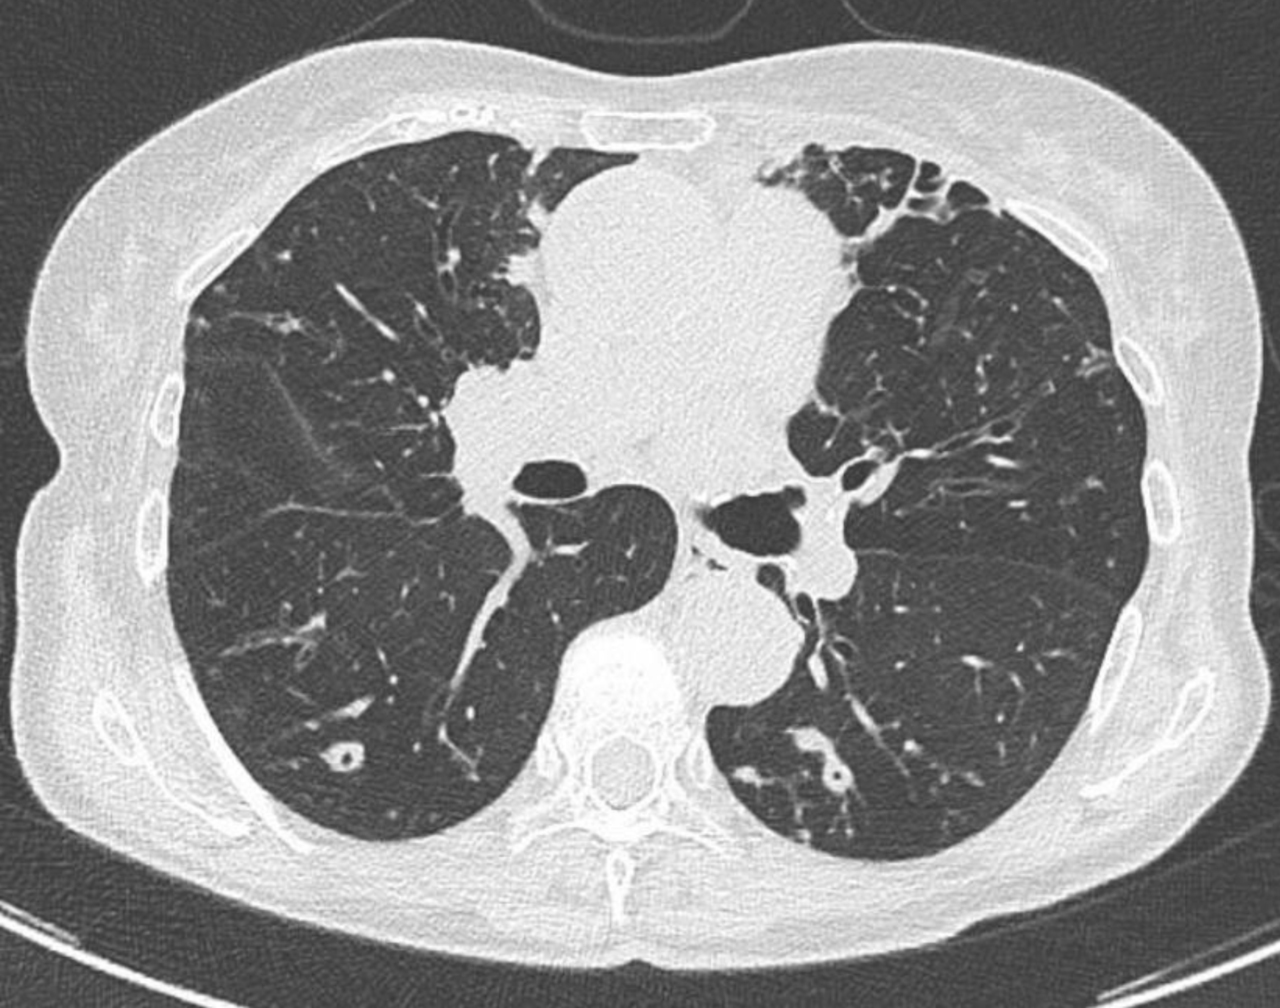

Vous réalisez donc les examens complémentaires suivants : – ETT sans anomalie notable – notamment pas de lésion valvulaire identifiée ; – fond d’œil sans foyer de rétinite ; – charge virale sérique CMV négative. Charge virale sérique EBV à 1,5 log ; – PCR nasopharyngée SARS-CoV-2, influenza et virus respiratoire syncytial (VRS) négative. Vous réalisez une TDM-TAP injectée qui ne retrouve pas d’anomalie notable à l’étage sous-diaphragmatique, notamment pas de foyer profond ni de polyadénopathie. Pas de lésion parenchymateuse hépatique ou splénique. À l’étage thoracique, vous identifiez en revanche ces lésions : Figure (Julien Derdevet, La Revue du Praticien)

La présence de nodules pulmonaires chez un sujet immunodéprimé – en dehors des causes tumorales – peut faire évoquer plusieurs étiologies infectieuses – bactériennes (Cocci à Gram positif ou germes intracellulaires, mycobactéries typiques (M. tuberculosis) ou atypiques, nocardiose...), fongiques (aspergillose, mucormycose, cryptococcose, histoplasmose, coccidioïdomycose...) voire virales. L’examen diagnostique le plus rentable reste donc dans cette situation le LBA. Plusieurs examens non invasifs peuvent toutefois être au préalable réalisés : l’antigénémie sérique galactomannane permet de diagnostiquer une infection à Aspergillus spp. (seul ou en faisant le rapport LBA/sérum), la PCR mucorale sérique a une très bonne valeur diagnostique pour les mucormycoses... Idem pour l’antigène cryptocoque sérique. Le bêta-D-glucane – marqueur antigénique pour presque toutes les infections fongiques en dehors de la cryptococcose et des mucormycoses – serait en revanche ici peu utile, puisque probablement positif dans le contexte de candidémie récente. Il a par ailleurs une cinétique de décroissance lente, ce qui en fait un mauvais marqueur pour le suivi thérapeutique. Enfin, il faut noter que les réactifs sont obtenus à partir d’extraits (sang) de limules – une espèce en déclin de par sa surexploitation. Pour finir, si une réactivation d’une tuberculose latente vers une tuberculose maladie reste possible – surtout chez un sujet né avant les années 1970 – les tests IGRA ou intradermoréaction (IDR) restent de peu d’utilité pour différencier ces deux cadres nosologiques.

Vous réalisez donc un lavage broncho-alvéolaire. Les prélèvements bactériologiques, mycobactériologiques et virologiques reviennent négatifs ; de même que l’anatomopathologie, qui retrouve des cellules inflammatoires aspécifiques. La culture fongique revient positive à Aspergillus fumigatus, avec un antigène galactomannane dans le LBA positif à 1,2. Les PCR mucorales dans le LBA sont négatives. L’antigène galactomannane plasmatique est également positif à 0,9 ; avec des PCR mucorales et un antigène cryptocoque négatives dans le plasma.

Si le diagnostic d’une aspergillose invasive est parfois difficile, le cas de Mme S. répond ici aux critères d’hôtes, d’imagerie et microbiologiques tels que définis dans les critères EORTC/MSG – 2019 – notamment avec l’identification d’un Aspergillus fumigatus et un antigène galactomannane positif dans le LBA et en sérique. Si la caspofungine reste parfois active sur Aspergillus spp., il n’est pas recommandé en première intention (fongostatique avec une surmortalité comparée aux tri-azolés, cf. Recommandations ECMID/ECMM/ERS – 2017). Le traitement de l’aspergillose invasive repose donc en premier sur un tri-azolé (voriconazole, isavuconazole...). Bien qu’un peu spécialisée, la prise en soin des aspergilloses invasives demande quelques réflexes : – les atteintes du système nerveux central (SNC) ou des sinus ne sont pas rares (porte d’entrée ORL ou par angio-invasion), et fréquemment asymptomatiques. Un bilan d’extension doit donc être réalisé de façon systématique, avec une TDM des sinus et (dans l’idéal) une IRM cérébrale ; – Aspergillus spp. est un champignon filamenteux ubiquitaire dans l’environnement qui se développe à partir de matières organiques en décomposition. La réduction de l’exposition environnementale (pas de fleur ni de plante en intérieur, limiter les fruits en décomposition, lutte contre l’humidité et les moisissures, limiter le jardinage...) fait donc partie intégrante de la prise en soin ; – la résistance aux azolés (mutations TR34/L98H principalement) d’Aspergillus fumigatus – par exposition personnelle ou environnementale aux azolés – est un problème émergent de santé publique à considérer en cas d’échec thérapeutique sous voriconazole/isavuconazole.